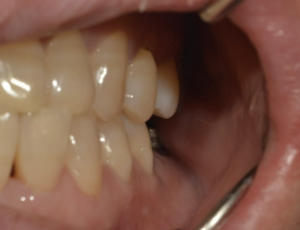

인덕원 임플란트치과, 뼈이식 후 얼마나 오래 유지될까? 안녕하세요.인덕원에서 임플란트 진료를 하고 있는 믿음치과 원장 손동근입니다.   최근 약 5년 전 치료를 받으셨던 환자분이 다시 내원하셨습니다. 당시에는 잇몸뼈가 부족해 고난이도의 뼈이식을...